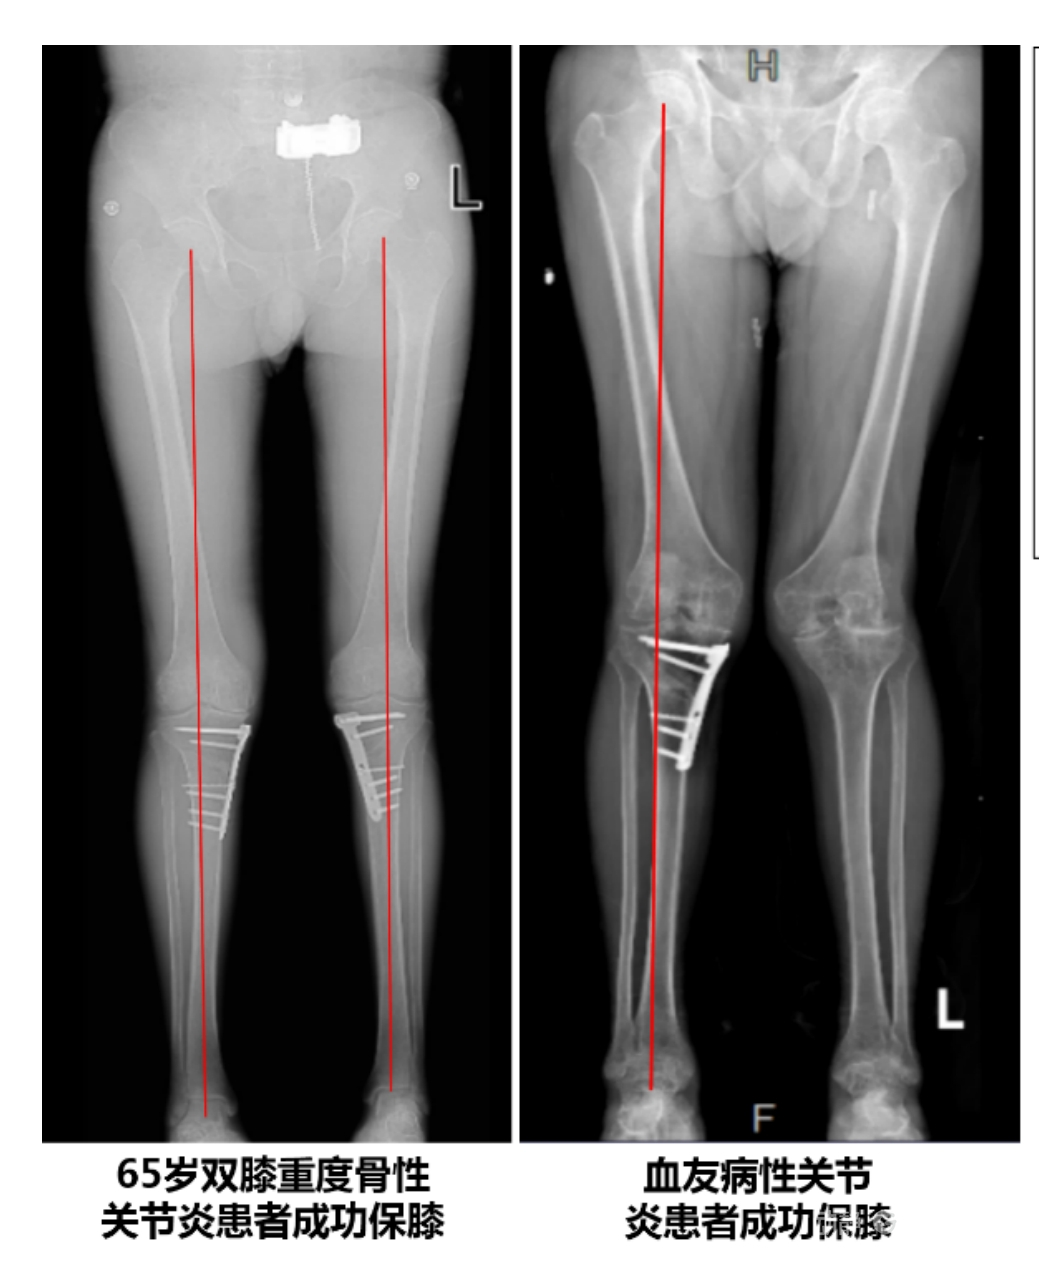

該手術具有經皮微創、保留原生膝關節結構、符合階梯治療原則等優勢,通過調整下肢力線可促進部分軟骨再生,術后關節功能接近正常(如下蹲、爬山),患者還能從事中重體力勞動。相比其他術式,其有效規避了髕骨低位、血管損傷、合頁骨折等潛在并發癥。

目前,APTT-HTO技術已成功應用于千余名患者,幫助保留自身膝關節。此類保膝手術適用于單間室膝關節炎患者(如 “羅圈腿”),核心是通過調整力線糾正畸形,減輕磨損間室壓力、發揮健康間室作用,延長膝關節壽命。若出現膝關節疼痛、保守治療無效且X線顯示關節間隙部分狹窄,建議及時就醫評估是否適合手術。

APTT-HTO脛骨高位截骨術